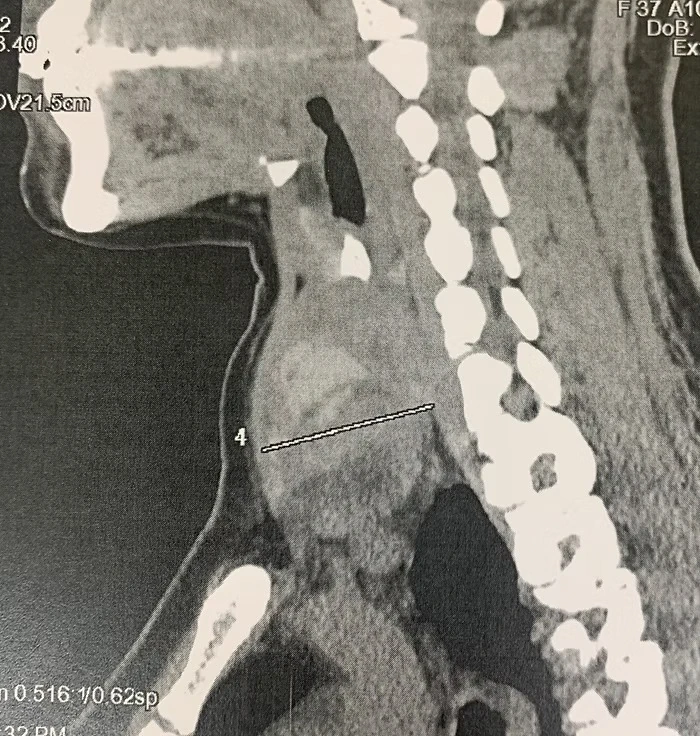

Case of a 37 years old Woman with 7cm Right Ishmic Nodes of the Thyroid Gland. Right Lobo-Isthmectomy was performed with the TOETVA procedure allowing no scar in neck.